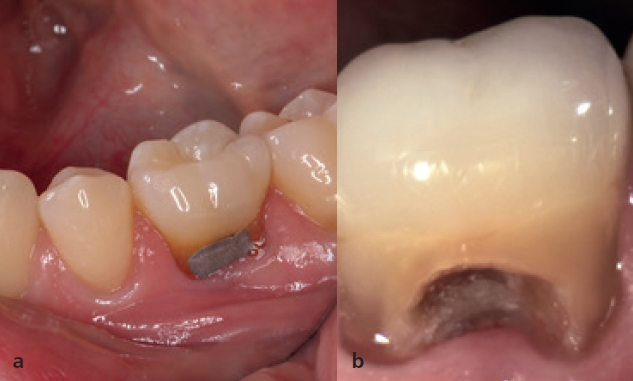

Eine 36-jährige Patientin stellte sich mir mit einem gefüllten Milchzahn an Position 85 vor. Der Zahn war aufgrund einer Sekundärkaries mit folglicher Pulpanekrose nicht erhaltungswürdig und sollte aufgrund der Nichtanlage des Zahnes 45 durch ein Implantat ersetzt werden (Abb. 1a und b). Zielsetzung war eine Sofortimplantation sowie die Sofortversorgung des Implantats. Eine andere Möglichkeit wäre eine kieferorthopädische Behandlung zum teilweisen oder vollständigen Lückenschluss gewesen oder alternativ die klassische Versorgung mittels einer 3-gliedrigen Brücke, jedoch bei unversehrten Pfeilerzähnen. Beide Konzepte schieden patientenseitig aus.

Obwohl ursprünglich als Sofortimplantation geplant, erfolgten die schonende Extraktion (Abb. 3) und die Implantation im Abstand von einer Woche. Das Ziel war es, die apikale Ostitis mit kurz vor dem OP-Termin beginnender bukkaler Schwellung abheilen zu lassen und eine ausreichende Entzündungsfreiheit zu erreichen (Abb. 7). Beim Einsetzen des Implantats kam die Bohrschablone zum Einsatz. Um die Lagestabilität der Schablone zu gewährleisten, war es wichtig, diese ausreichend groß zu dimensionieren (Auflage Zahn 33 bis 46); Sichtfenster ermöglichen es dabei, die planmäßige und vollständige Auflage der Schablone auf dem Zahnbogen jederzeit zu kontrollieren.